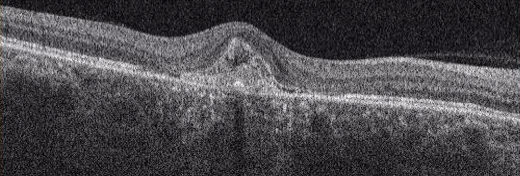

下図 / 加齢黄斑変性のOCT図

三次元眼底画像解析装置(OCT)

網膜の断面を観察して、網膜やその下の新生血管などの状態を立体的に観察します。